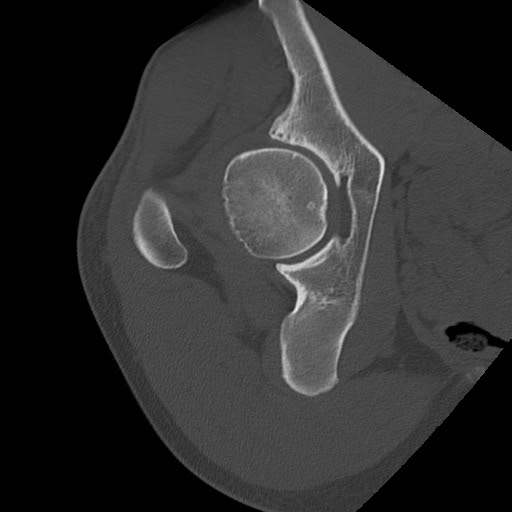

From radiologycases.blogspot.com

Radiology Cases CAM Type FAI What Is Cam Type Fai femoroacetabular impingement (fai) is a condition in which extra bone grows along one or both of the bones that form the hip. what causes femoroacetabular impingement? Fai occurs when the space between the ball (femur) and socket (acetabulum). Cam lesion, in which the head of the femur is not shaped properly. there are three types of fai: What Is Cam Type Fai.